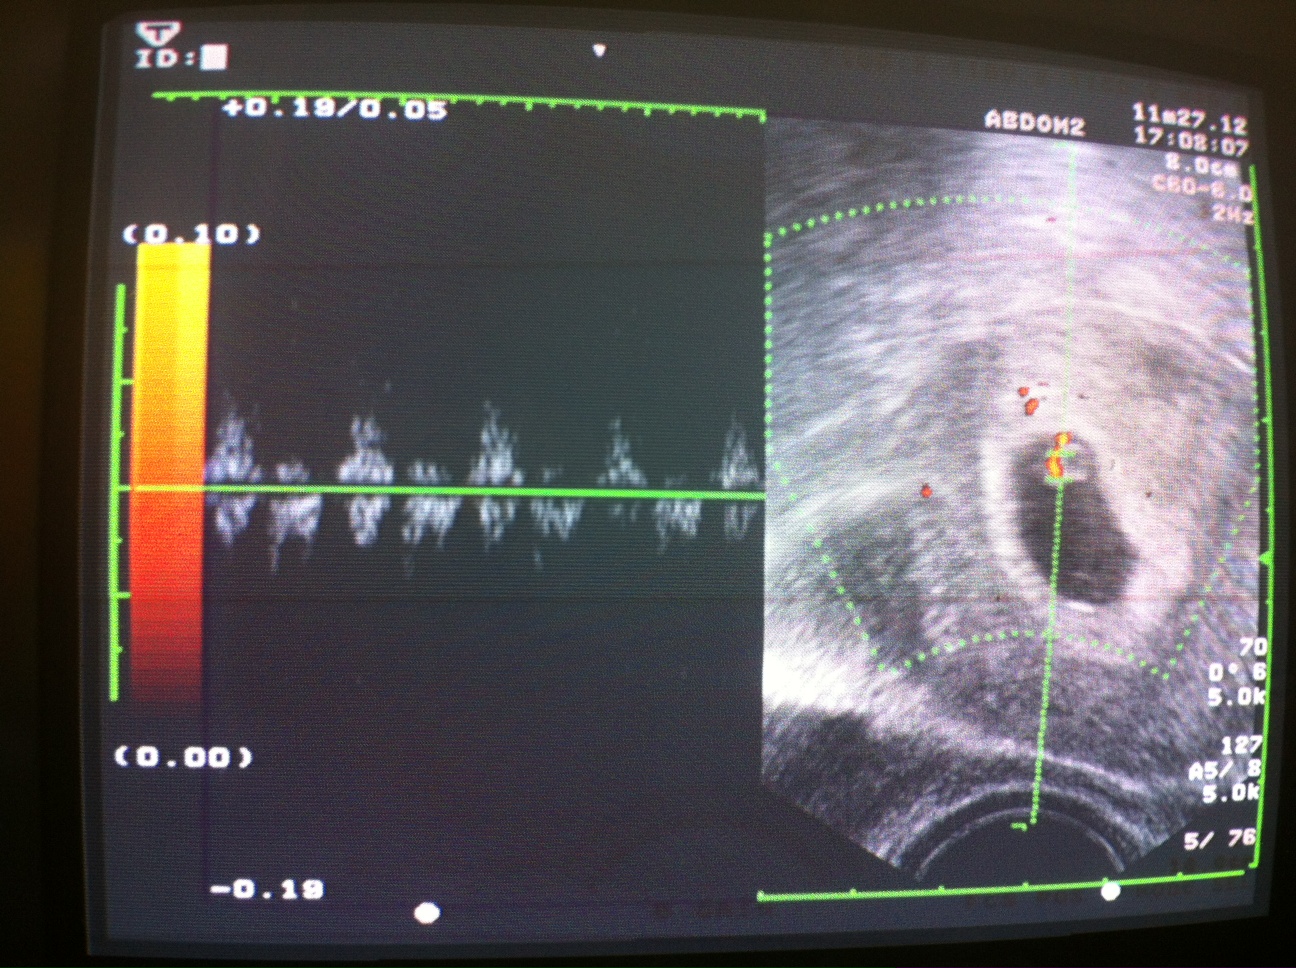

以下為化名,48歲王小姐美如跟先生結婚多年,她跟先生是在日本讀書的時候認識,先生在日本東京當老師,在去年3月311大地震的時候,因為學校地震放假,他就來台灣找太太度假,順便把他自己精子冷凍在本院的精子銀行,基於太太年紀的因素,她曾經做過多次試管嬰兒都沒有成功,最近在彰化市博元婦產科進行試管嬰兒,我們植進去三個胚胎,其中有一個4AA級胚胎,今天提前兩天驗孕,抽血報告已經是β-HCG為124,用這個數據來推應該是單胞胎,我在這裡恭喜她,在她48歲這年齡還能做試管嬰兒成功,比較特殊的是,我們所使用的是從日本東京的教書的先生,在本院冷凍精子近一年半試管嬰兒懷孕成功,非常恭喜她!